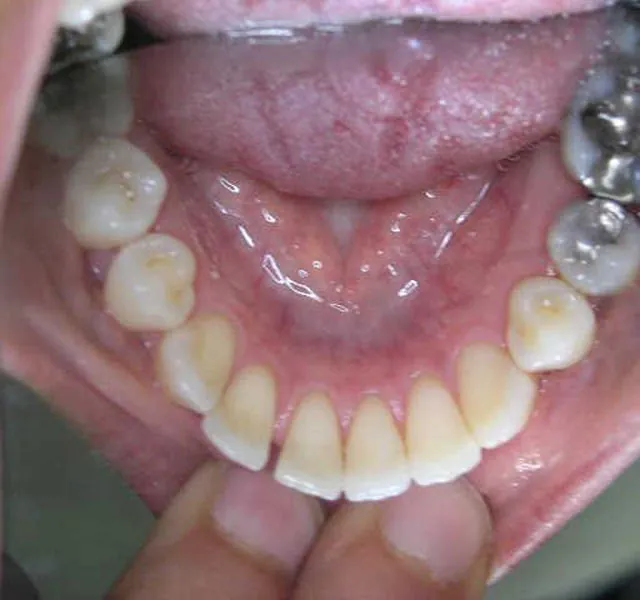

Patientin (42 Jahre) mit Engstand, Schmalkiefer, Fontaler Kant- und Kreuzbiss

Unterkieferzahnbogen